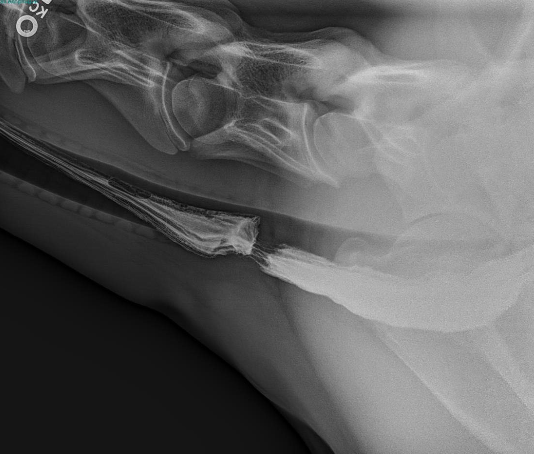

how are esophageal strictures diagnosed?

endoscopy, barium swallow studies

how is a esophageal diverticulum diagnosed?

barium swallow

how is megaesophagus diagnosed in horses?

presumptive diagnosis via clinical signs

definitive diagnosis via endoscopy, esophogram (barium swallow)